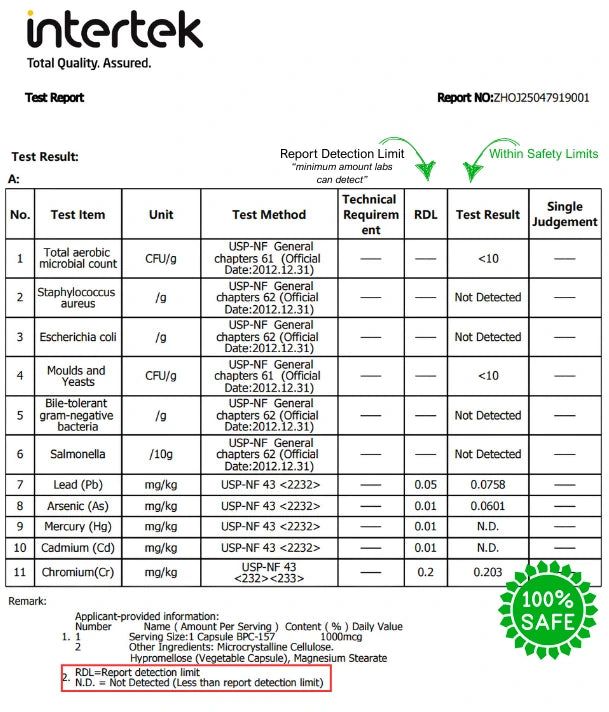

9. Is AzureVital’s BPC-157 3rd party tested for purity?

9. Is AzureVital’s BPC-157 3rd party tested for purity?

Yes. Every batch is third-party tested for purity, identity, and contaminants. We publish results upon request and believe you deserve to know exactly what's in your supplement — no hidden ingredients, no compromises.